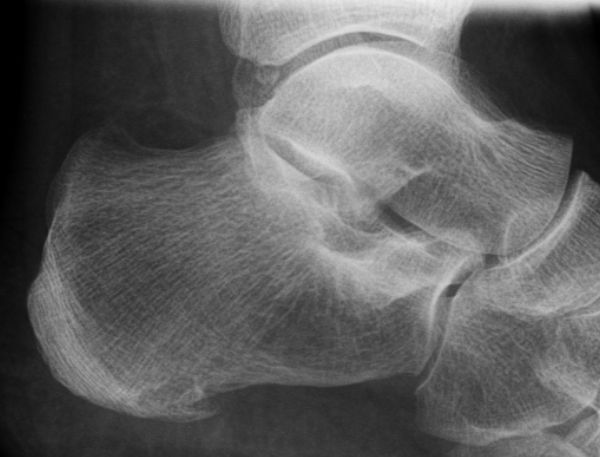

ausgeprägter dorsaler und asymptomatischer plantarer Fersensporn![]() |

||||||